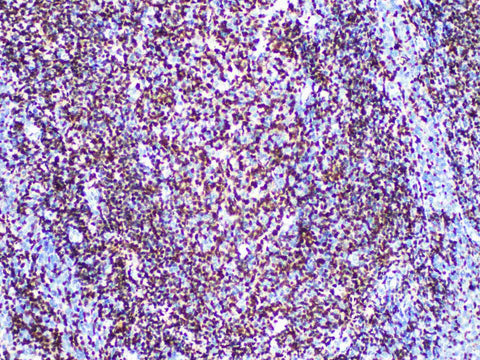

Oct-2 Monoclonal Antibody

Reactivity Human

Applications IHC-P

Tissue Specificity Tonsil

OCT2 is a B cell specific transcription factor, which participates in the regulation of Ig gene expression, and is related to the regulation of many B cell proliferation and differentiation genes. OCT2 is highly expressed in all mature B cells, and low expressed in pre-B cells, T cells and medullary cells, it is a sign of B cell differentiation.